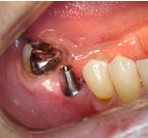

インプラント

第3の歯インプラントも診断が一番大切。適切な治療が成功の鍵です。

入れ歯から開放されて快適な食生活を送って下さい。残っている歯にとっても最適な治療法です。

- 施術前

- 施術後

- イメージ